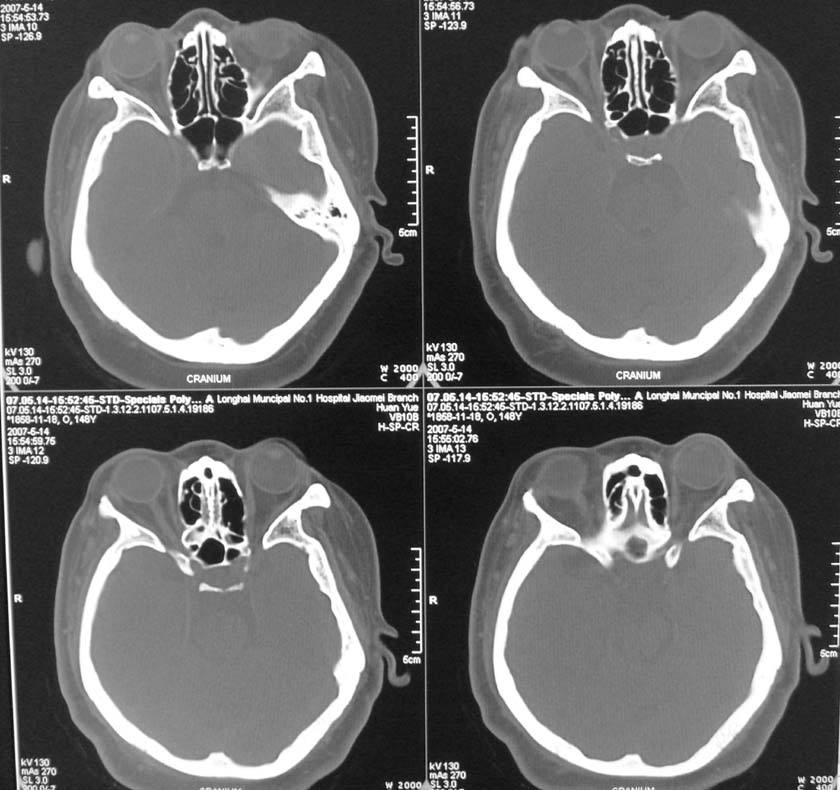

以下是引用天南地北在2007-5-15 23:30:00的发言:[br]看不出来什么[br]建议冠面增强扫描,或mri检查

以下是引用郭凯在2007-5-16 0:17:00的发言:[br]看不到,如果临床支持的话还是做mri看一下吧,对垂体微腺瘤比较敏感.[br]ct上看不到不能乱报.

以下是引用jiangjing在2007-5-16 11:06:00的发言:[br]看不出来什么[br]建议冠面增强扫描,或mri检查